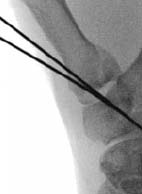

経皮的ピンニング

骨折の整復後に経皮的ピンニングを行う方法は、依然として一般的な手術固定法です。キルシュナーワイヤー(Kワイヤー)固定は、低侵襲性の選択肢であり、外科医が安定化パターンを柔軟に選択でき、軟部組織への損傷を最小限に抑えることができます。しかし、Kワイヤーは、スクリュー、プレート、釘を用いたより安定した固定法と比較して、固定が失われるリスクが高くなります。